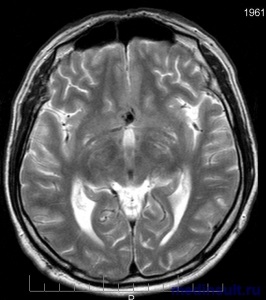

hemoragie subarahnoidă (SAH) este considerată astăzi un sindrom clinic, care este cauzata de ruptura de sânge și acumularea de subarahnoidian (subarahnoidiene) spațiu al creierului și / sau măduvei spinării, care se referă la hemoragie intracraniană (accident vascular cerebral acut pe tip hemoragic). Există două tipuri de SAH - hemoragie subarahnoidiană spontană și traumatice.

Cauza principală a hemoragiei subarahnoidiene (80%) dintr-o pauză bruscă sau anevrism saccular vascular cerebral sau malformație vasculară (4 până la 5%) atunci când fistule arteriovenoase și Cavernomas care apar spontan (hemoragie subarahnoidiană spontană) sau ca urmare a unor traumatisme craniene (adesea la copii și adolescenți ).

Astăzi a constatat că sângerarea se produce din cauza ruperea completă deteriorat vas de proces patologic sau parțial pereții lacrimal creierului arterei meningeale, ceea ce duce la o perturbare completă a integrității vasculare cerebrale sau formarea progresivă a anevrismelor bursting pe fondul creșterilor bruște ale tensiunii arteriale sau a bolilor vasculare congenitale (anevrism congenital sau malformații vasculare). anevrismele congenitale sunt mai frecvent localizate în zona de bifurcația arterelor de ramificare baza mare a creierului.

Practic flux de sânge se acumulează în principal în spațiul de bază a cisternelor subarahnoidiană - hemoragie subarahnoidiană bazală în creier. La ruperea unui anevrism sange se raspandeste rapid in lichidul cefalorahidian cu aparitia ulterioara a exprimat spasm al arterelor cerebrale ale dezvoltării creierului de edem, urmat de moartea neuronală.

anevrism cerebral gasit adesea anevrism saccular, vasculare avand o forma cu fundul pungii, un corp și un gât cu dimensiuni în diametru de la câțiva milimetri până la 1-2 centimetri si anevrismele gigant - 2 centimetri în diametru.